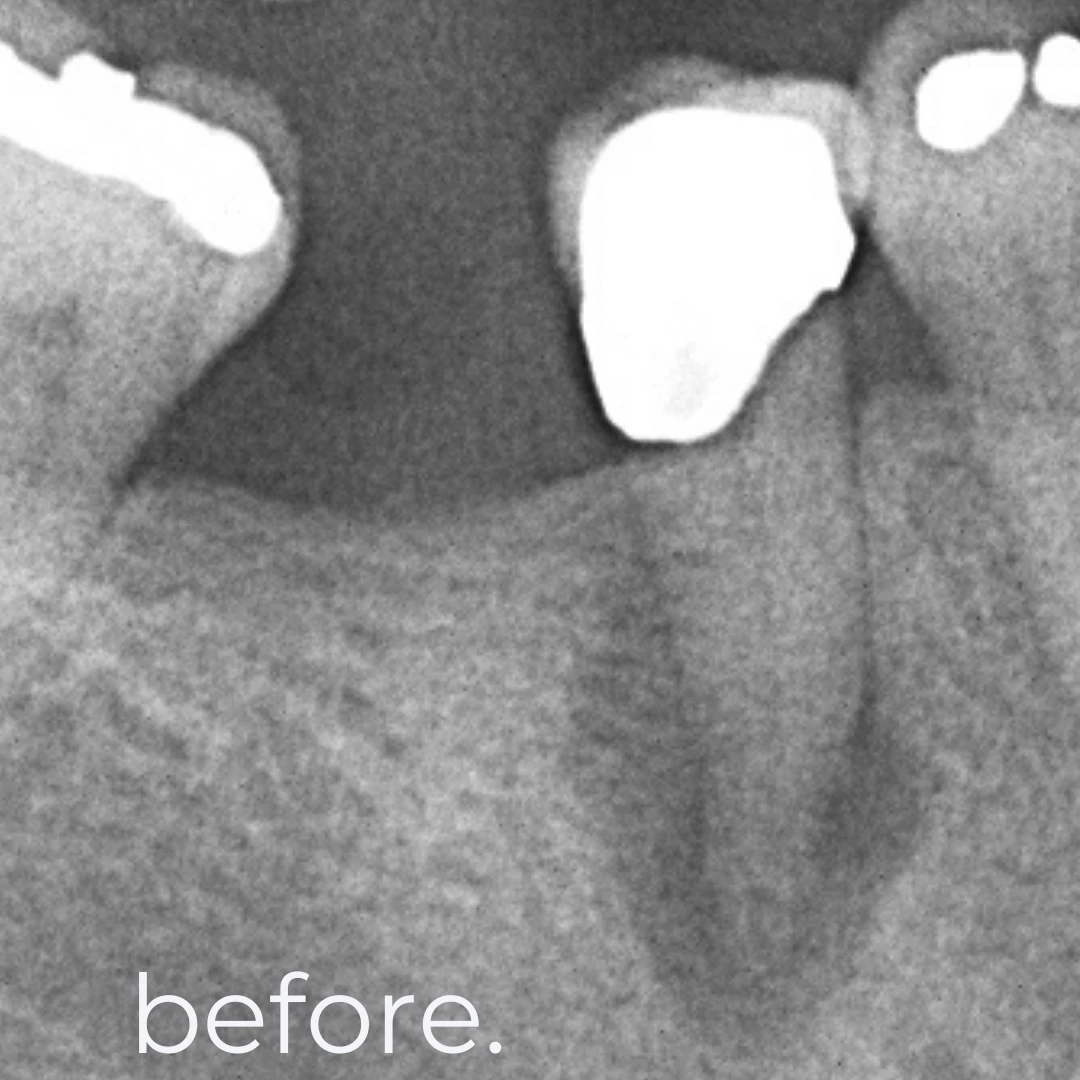

A root canal treatment is a minimally invasive procedure designed to remove infected or inflamed dental pulp, disinfect the root canal, and seal it with a biocompatible filling. This treatment eliminates pain while preserving your natural tooth structure, preventing the need for extraction and maintaining oral health and function.

🦷 Phase 1: Cleaning & Disinfection – Removal of infected pulp and thorough sterilization